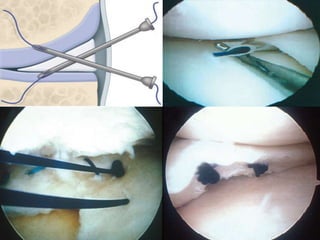

• Meniscal repair

1-inside-out technique

2-all-inside technique (suture devices with plastic or

3-outside-in repair

Treatment • Meniscalrepair – approach 1-inside-out technique – considered gold standard – medial approach to capsule – lateral approach to capsule 2-all-inside technique (suture devices with plastic or bioabsorbable anchors) – most common – many complications (device breakage, iatrogenic chondral injury) 3-outside-in repair – useful for anterior horn tears – open repair – uncommon except in trauma, knee dislocations